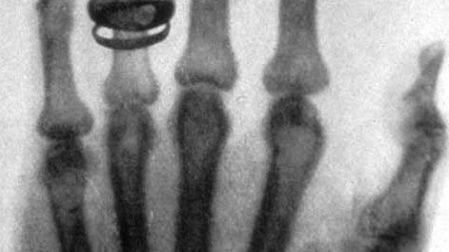

El descubrimiento de los rayos X

La carrera de Wilhelm Conrad Roentgen estuvo plagada de dificultades. Cuando fue estudiante en Holanda fue expulsado de la Escuela Técnica de Utrecht por una broma cometida por otro estudiante.

Sus experimentos en Würzburg se centraron en los fenómenos de luz y otras emisiones generadas por la descarga de corriente eléctrica en los llamados "tubos de Crookes", bombillas de vidrio con electrodos positivos y negativos, sin aire, que muestran un brillo fluorescente cuando pasa una corriente de alto voltaje. eso. Estaba particularmente interesado en los rayos catódicos y en evaluar su alcance fuera de los tubos cargados.

El 8 de noviembre de 1895, Roentgen notó que cuando protegió el tubo con cartón negro pesado, la luz verde fluorescente hizo que brillara una pantalla de platinobario a nueve pies de distancia, demasiado lejos para reaccionar a los rayos catódicos como él los entendía.

Determinó que la fluorescencia era causada por rayos invisibles que se originaban en el tubo de Crookes que estaba usando para estudiar los rayos catódicos (más tarde reconocidos como electrones), que penetraban en el papel negro opaco que envolvía el tubo.

Otros experimentos revelaron que este nuevo tipo de rayo era capaz de atravesar la mayoría de las sustancias, incluidos los tejidos blandos del cuerpo, pero dejaba visibles los huesos y los metales. Una de las primeras placas fotográficas de sus experimentos fue una película de la mano de su esposa Bertha, con su anillo de bodas claramente visible.